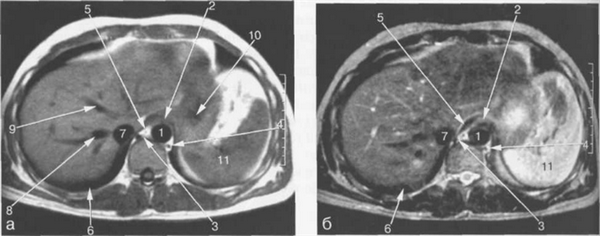

Рис. 11.11. МРТ брюшной полости в аксиальной плоскости на уровне печеночных вен.

1 — аорта; 2 — желудок; 3 — хвостатая доля печени; 4 — левая ветвь воротной вены; 5 — передние сегменты правой доли печени; 6 — задние сегменты правой доли печени; 7 — нижняя полая вена; 8 — правая печеночная вена; 9 — правая ветвь воротной вены; 10 — левая доля печени; 11 — селезенка; 12 — диафрагма.

Правая печеночная вена расположена в правой межсегментарной борозде, которая отделяет друг от друга передние и задние сегменты правой доли печени (рис. 11.12, 11.13). Левая печеночная вена располагается в левой межсегментарной борозде и разделяет внутренний и наружный сегменты левой доли печени (см. рис. 11.9). Серповидная связка также может использоваться в качестве ориентира, разделяющего внутренний и наружный сегменты левой доли печени.

Хвостатая доля печени располагается кзади и кнаружи относительно нижней полой вены (см. рис. 11.12). Кровоснабжение хвостатой доли осуществляется ветвями как правой, так и левой печеночных артерий и воротной вены. Венозный дренаж происходит в НПВ.

Рис. 11.12. МРТ брюшной полости в аксиальной плоскости на уровне поджелудочной железы.

1 — аорта; 2 — нижняя полая вена; 3 — селезеночная вена; 4 — хвост поджелудочной железы; 5 — желудок; 6 — селезенка; 7 — толстая кишка; 8 — задние сегменты правой доли печени; 9 — задние сегменты ветви правой воротной вены; 10 — передние сегменты ветви правой воротной вены; 11 — медиальные сегменты левой доли печени; 12 — латеральные сегменты левой доли печени; 13 — левый надпочечник; 14 — верхний полюс левой почки.

Рис. 11.13. МРТ брюшной полости в аксиальной плоскости на уровне внутрипеченочных ветвей воротной вены.

1 — аорта; 2 — нижняя полая вена; 3 — селезеночная вена; 4 — тело поджелудочной железы; 5 — желудок; 6 — селезенка; 7 — левый надпочечник; 8 — правый надпочечник; 9 — задние сегменты ветви правой воротной вены; 10 — медиальные сегменты левой доли печени; 11 — верхний полюс левой почки.